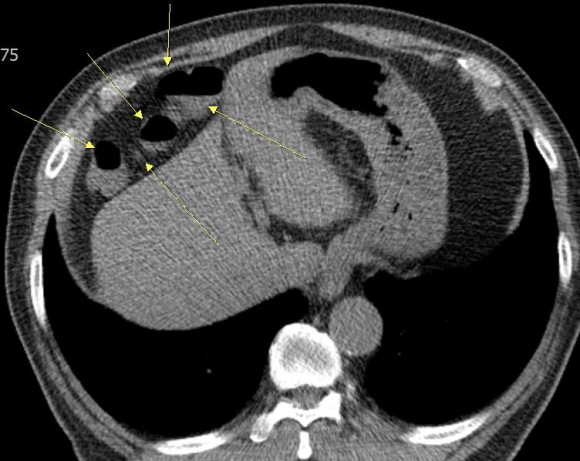

최근 이분의 여러 사진을 검토하는 과정에서 위 사진처럼 횡격막과 간 사이에 대장이 끼어 있는 것이 관찰되었으며, 이 마직막 사진에서는 그 부분의 대장에는 장의 약간의 마비를 시사하는 수면을 볼 수 있다.

이 분의 증상이 이른바 Chilaiditi 증후군이 아닐까 의심된다.이 분처럼 대장이 횡격막과 간 사이에 끼어 있는 현상을 Chilaiditisign이라고 한다. 이것이 확실한 증상을 가져온다는 것이 확인되면 Chilaiditi 증후군으로 진단한다. 그러나 이 병은 진단이 매우 어렵고 증상도 다양하다.

이 병은 19010년 그리스 방사선 의사인 Dimitrios Chilaiditi가 처음 기술했다 뚜렷한 증상은 오른쪽 윗배가 아픈데 다른 병으로는 설명할 수 없으며 이런 현상이 보이자 이 병을 의심한다